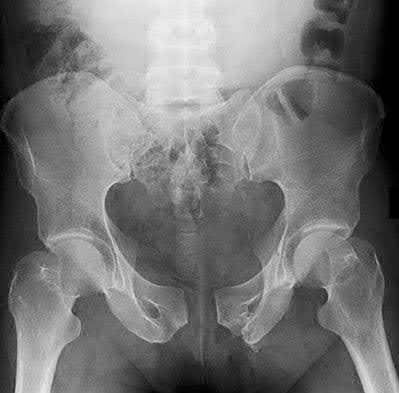

3. # Which of the following is not an appropriate implant for treatment of the fracture seen in Figure A?

1. Cephalomedullary nail

2. External fixation

3. Proximal femoral locking plate

4. 95 degree blade plate

5. Sliding hip screw Corrent answer: 5

The image shows a reverse obliquity intertrochanteric hip fracture.

According to the referenced article by Haidukewych et al, unstable peritrochanteric hip fractures have a worse outcome (failed in 9/16 cases) if treated with a sliding hip screw. Two additional factors that were found to have a strong correlation with postoperative failure (nonunion, loss of reduction) were poor reduction and poor implant placement. In this study, fixed angle devices were superior. Intramedullary fixation has the added advantage of a shorter lever arm and less potential for fracture collapse and limb shortening.

The IMN also acts as a medial buttress.

According to Sanders et al, the dynamic condylar screw (DCS) can also be used in subtrochanteric models, but should not be used if extensive comminution is seen, as they reported a high failure rate with DCS in these fractures if highly comminuted. They report a 77% overall union rate with this device.